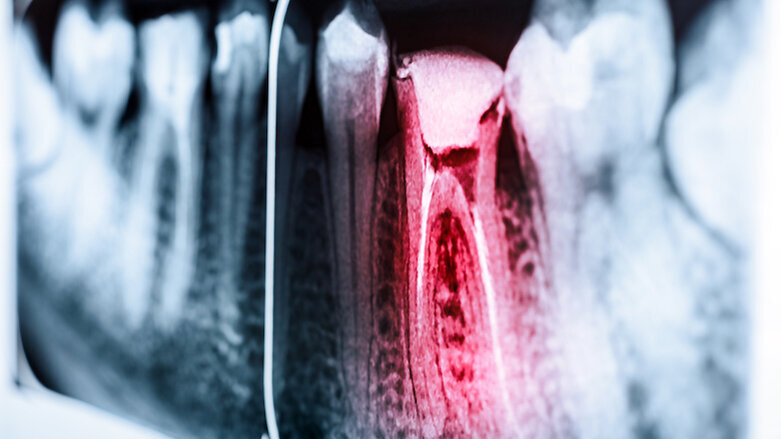

MENSFILD, Kontektikat, SAD: U nadi da će pronaći bolji način za otkrivanje zubne boli, tim naučnika sa Univerziteta u Konektikatu trenutno razmišlja da na nov način kvantifikuje zubobolju i razviju za pacijente prilagođen pametni senzor za merenje. Istraživači, sa Klinike za endodontologiju i Odeljenja za biomedicinsko inženjerstvo na Stomatološkom fakultetu Univerziteta Konektikat nedavno su dobili sredstva koja podržavaju ovo istraživanje.

Dr I-Ping Chen, vanredni profesor za oralno zdravlje i dijagnostičke nauke, i dr Ki Chon, profesor i šef odeljenja za biomedicinsko inženjerstvo, sarađivali su na ovom projektu koji je privukao 462.964 USD donacije od Nacionalnog instituta za stomatološka i kraniofacijalna istraživanja. Kao endodont, dr Chen se brine za pacijente kojima je potrebna endodontska terapija. Međutim, ona i drugi stomatolozi se u velikoj meri oslanjaju na pacijentovo subjektivno mišljenje da bi procenili nivo pacijentovog bola.

"Oslanjanje na reakciju pacijenta, koja je više subjektivna, može biti problematično, posebno kada pacijenti ne mogu komunicirati sa svojim stomatolozima - poput dece, pacijenata sa invaliditetom i pacijenata koji ne govore dobro jezik zemlje u kojoj žive“, rekla je dr Chen.

Na ideju je došla dr Chen kada je saznala da dr Chon koristi komercijalno dostupan uređaj u svojoj laboratoriji koji može otkriti aktivnost simpatičkog nervnog sistema tj. način na koji telo registruje bol. Uređaj se trenutno koristi za otkrivanje provodljivosti kože, što ima potencijal da pokazuje efekte promena nivoa bola na pacijenta. Upotreba ovog kvantitativnog merenja za stomatološku dijagnostiku i otkrivanje zubnog bola je potpuno nov koncept.